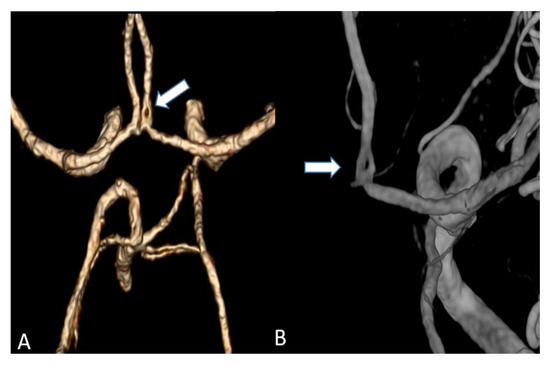

Figure 5.

(A) Volume rendering of an anterior cerebral artery fenestration acquired by an UHR-CT (B) Three-dimensional (3D) digital subtraction angiography (DSA) to confirm arterial fenestration in (A), which is often not detected by normal resolution CTAs.

Studies on coronary artery and small visceral artery CTAs [11,12] have recently shown that the UHR-CT system is highly suitable for a significant improvement in image quality, SNR, CNR and an enhanced vascular imaging. Our investigation, which to our best knowledge represents the first study to evaluate image quality, contrast and delineation of the supra-aortic vessels and the small perforating arteries, confirms the excellent qualification of the UHR-CTA as a diagnostic tool in radiological and vascular imaging. Hence, the use of UHR-CTA will be of high value in various clinical settings, especially when a high resolution is inevitable for an accurate diagnosis and optimized patient care. In detail, advances in the diagnosis of aneurysms and steno-occlusive diseases may be reached, especially when looking at aneurysm configuration, and peculiarities or irregularities of the of aneurysm wall. UHR diagnostics may additionally improve pre-invasive planning of subsequent digital subtraction angiographies and interventions, enabling earlier and more individualized treatment decisions. An additional benefit will arise from a substantially reduced radiation exposure due to the omission or the time reduction in follow-up examinations.